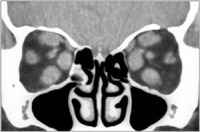

En la TC existen hallazgos en un 70% de los casos y característicamente se observa un engrosamiento fusiforme del vientre muscular que respeta la inserción tendinosa del globo. Los músculos recto inferior y recto interno son los más frecuentemente afectados. La afectación del recto lateral y los músculos oblicuos es menos frecuente. La grasa orbitaria puede estar aumentada en estos pacientes (Figura 4). La RM permite valorar además la actividad inflamatoria de la enfermedad.

Figura 4. Oftalmopatía tiroidea: TC orbitario sin contraste. Reconstrucción en plano coronal en la que se aprecia un engrosamiento simétrico de los músculos rectos medial, superior e inferior, respetando los músculos rectos laterales.